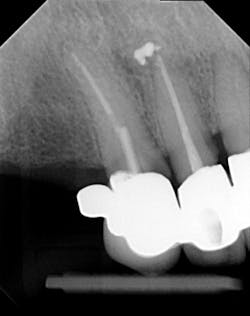

Dentition: Upper anterior splinted crowns had open margins and caries. Radiographs confirm decay, along with open margins (figures 6–11). Lower incisal anterior wear noted (figure 2).

Periodontium: Probing depths normal on all teeth, with some bleeding noted around the margins of the upper splinted crowns. Slight to moderate bone loss on lower anterior teeth.